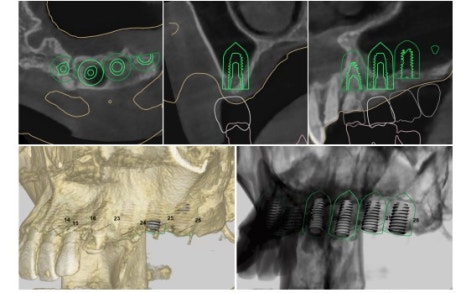

그로 인해 3D 임플란트 내비게이션이라는 장치가 있습니다.

이런 식으로

환자분의 데이터를 바탕으로 모의 수술을 하고

그로 인해 임플란트 수술 방향을 정한 상태로 수술을 들어갑니다.

뼈가 너무 얇지만 광범위한 뼈이식 동시에

임플란트까지 식립하는 것을 목표로 하고

수술시간 단축을 위해 3D 내비게이션 가이드를 제작했습니다.

환자분의 데이터를 통해

아래와 같은 3D 내비게이션 가이드를 제작합니다.